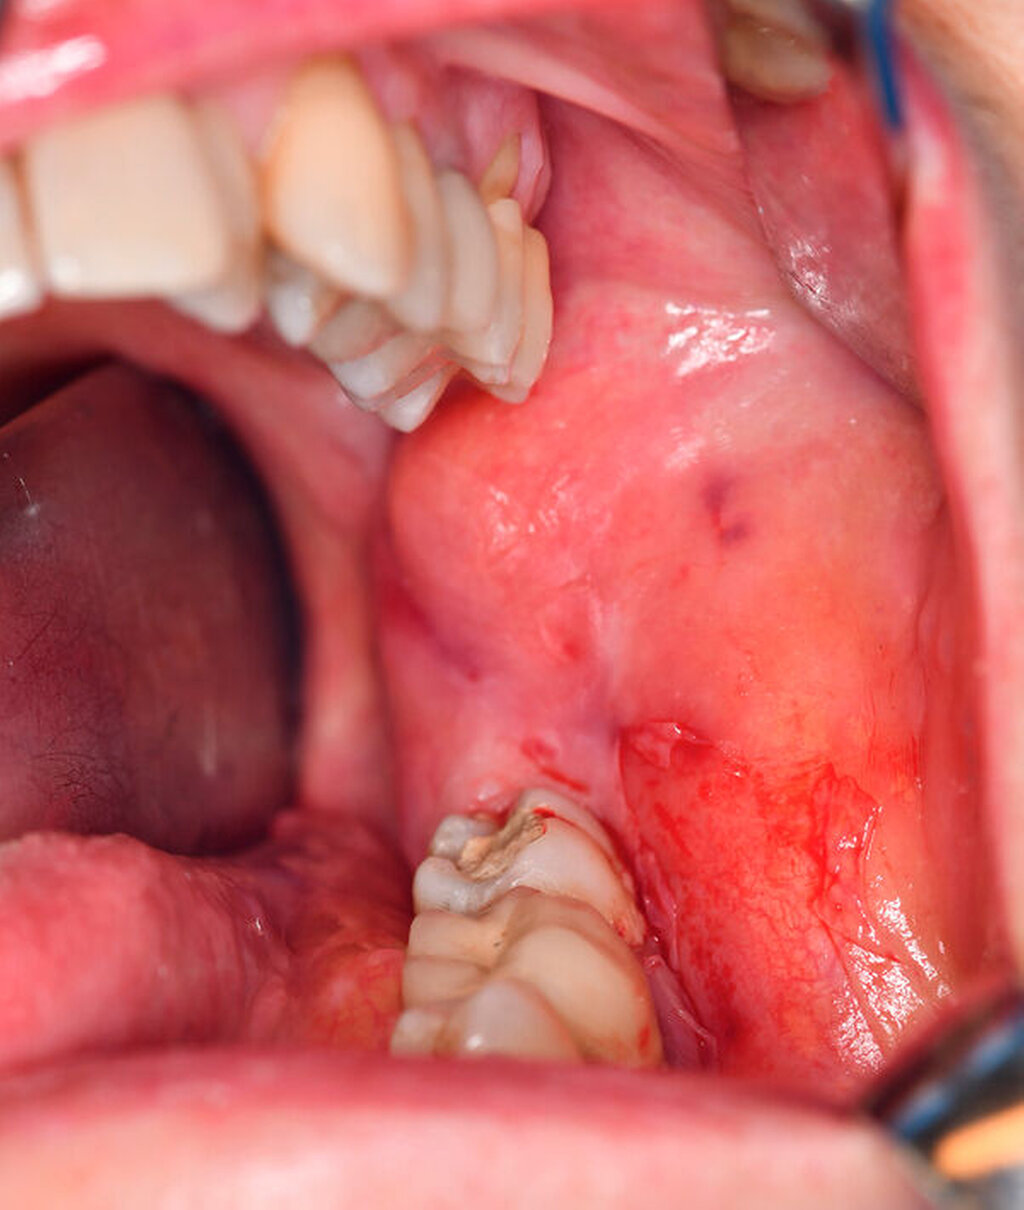

Aufgrund der erhöhten Frakturgefahr bei bereits ausgedehnter Knochenresorption wurde mit der Patientin nach Anfertigung der komplettierenden 3-D-Bildgebung (digitale Volumentomografie) ein zeitnaher Termin zur Diagnosesicherung durch Probeentnahme in Allgemeinanästhesie vereinbart (Abbildung 2). Bereits in der darauffolgenden Woche konnte der Eingriff durchgeführt und die intraoperativ gut erreichbare, klinisch als follikulär anmutende Zyste in toto im Sinne einer Zystektomie mit Osteotomie des Zahnes 38 entfernt werden. Hierbei stellten sich das Vestibulum als solide verstrichen und die darunterliegende Kortikalis nach Schleimhautpräparation pergamentartig ausgedünnt dar (Abbildung 3). Auf eine zusätzliche Stabilisierung mittels Osteosyntheseplatte wurde bei ausreichendem Restknochen verzichtet.

Während kleinere Zysten vornehmlich via Zystektomie und Extraktion des retinierten Zahns (bei im Durchbruch befindlichen Zähnen sollte eine isolierte Zystenbalgentfernung mit kieferorthopädischer Eruptionsunterstützung zum Zahnerhalt in Erwägung gezogen werden) behandelt werden, ist die Zystostomie zur primären Reduktion des knöchernen Zugangstraumas mit sekundärer Zystektomie nach histopathologischer Diagnosesicherung das Therapiekonzept der Wahl [Neville et al., 2016]. Da im vorliegenden Fall die vestibuläre Knochenlamelle bereits pergamentartig ausgedünnt war und sich der Zystenbalg problemlos in toto enukleieren ließ (Abbildungen 3a bis 3d), entschied man sich hier für eine primäre Zystektomie. Eine engmaschige andauernde Nachsorge ist nach histopathologischer Befundsicherung nicht zwingend erforderlich und kann im Rahmen der allgemeinen zahnärztlichen Routineuntersuchungen durchgeführt werden.